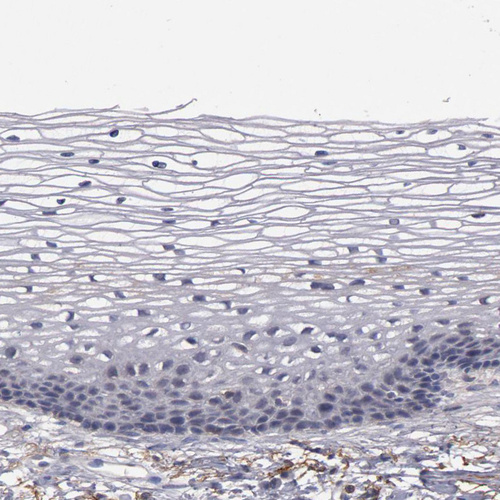

Immunohistochemistry analysis in human liver and prostate tissues using HPA002027 antibody. Corresponding MBL2 RNA-seq data are presented for the same tissues.